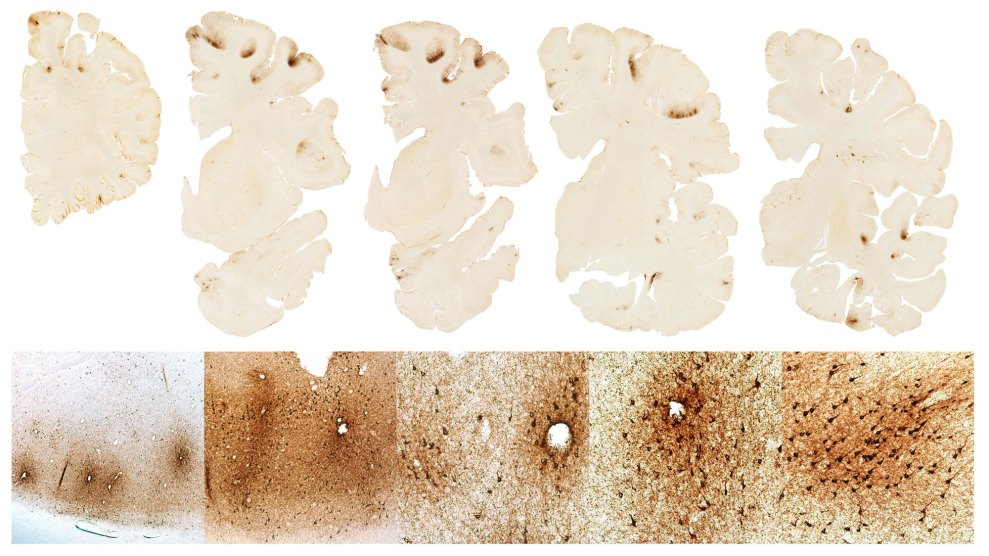

Scans of Aaron Hernandez's brainBoston University CTE Center

CTE can only be diagnosed in an autopsy. A recent study found evidence of the disease in 110 of 111 former NFL players whose brains were examined.

CTE has been linked with repeated concussions and involves brain damage particularly in the frontal region that controls many functions including judgment, emotion, impulse control, social behavior and memory.